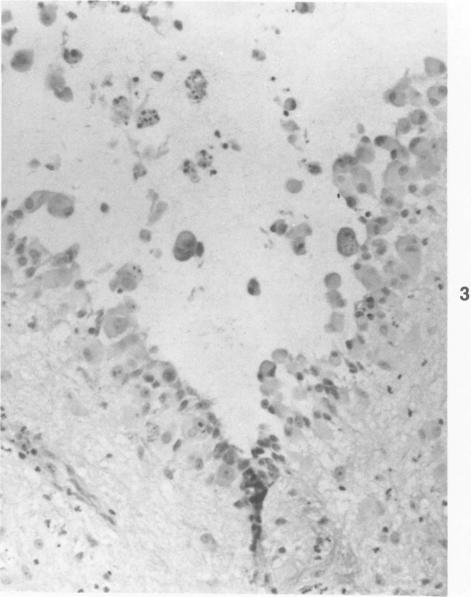

Rhesus monkeys experimentally infected with the lentivirus SIV/Delta become immunodeficient and often die of opportunistic infections. The most frequent of these is cytomegalovirus (CMV). The lesions due to reactivated CMV infection in 14 SIV-infected monkeys were reviewed. Changes due to CMV were observed in the brain, lung, lymph node, liver, spleen, small intestine, testicle, nerves, and arteries. Disseminated CMV infection in immunodeficient rhesus monkeys is a useful model for studying the pathogenesis, treatment, and prevention of similar infections in immunodeficient human beings.

实验感染慢病毒SIV/Delta的恒河猴会出现免疫缺陷,常死于机会性感染。其中最常见的是巨细胞病毒(CMV)。回顾了14只感染SIV的猴子因CMV感染再激活而出现的病变。在脑、肺、淋巴结、肝、脾、小肠、睾丸、神经和动脉中观察到了由CMV引起的变化。免疫缺陷恒河猴中的播散性CMV感染是研究免疫缺陷人类中类似感染的发病机制、治疗和预防的有用模型。